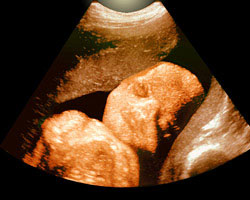

Já bem consolidado no terceiro trimestre, o bebé cada vez tem menos espaço para se mexer. Apetece-te ver como está dentro do útero? Em seguida oferecemos-te a imagem de uma ecografia e de um vídeo que te vão surpreender. Espanta-te!

Ecografia de 30 semanas